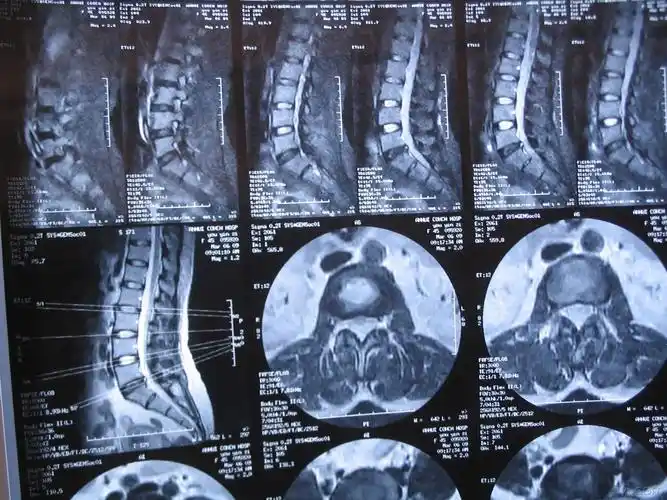

腰椎ct

腰椎椎管占位请大家会诊附有ct图片

术前腰椎ct

请教我读张腰椎ct片

冠状位腰椎ct平扫.

腰椎ct检查请讨论